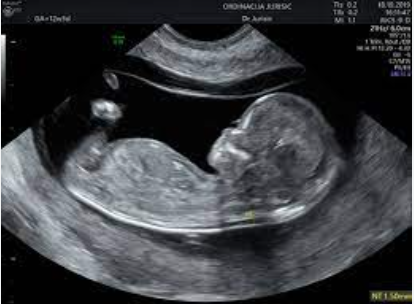

Doktor je nasmijano obavio pripremu za ultrazvuk i rekao: „Idemo vidjeti našu bebu.“ Marina se udobno smjestila na sto, srca punog nade da će čuti poznati ritam bebinog srca i možda prvi put vidjeti sitne obrise svog nerođenog djeteta.

Međutim, nakon nekoliko trenutaka tišine, doktor je zadržao pogled na ekranu i nagnuo se bliže. Lice mu se nije smijalo kao prije. Marina je osjetila kako joj se srce stislo.

„Na monitoru jasno vidim tri fetusa. Čestitam – nosite trojke!“

U trenutku, soba se zavrtjela. Marina je gledala ekran, pokušavajući razaznati oblike koji su se kretali u crno-bijelim sjenama. Trojke. Tri srca. Tri života. Tihi šok ispunio je prostor, a onda su krenule suze – suze nevjerice, straha, ali i neobjašnjive radosti.